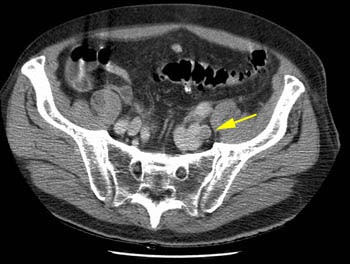

Pulmonary embolsim in a patient with left external iliac vein thrombosis

The patient shown below was post op from repair of an abdominal aortic aneurysm. The CT PE exam demonstrated emboli to the left lower lobe and right upper lobe (large clot) pulmonary arteries. The DVT portion of the exam detected clot in the left iliac vein- a finding which would not have been evident on lower extremity ultrasound. In patients that require an inferior vena caval filter the identification of clot within the iliac vessels or IVC can aid in the angiographic approach to filter placement.

A left external iliac vein clot was identified during the CT DVT exam (yellow arrow)